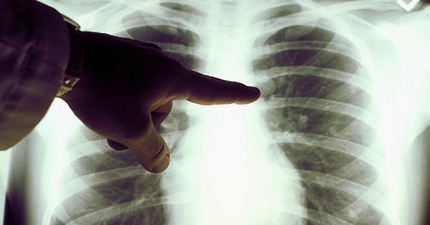

怕吵到小孩「堅持1習慣」 竟慘罹肺癌末期!她診間崩潰:只是想當好媽媽